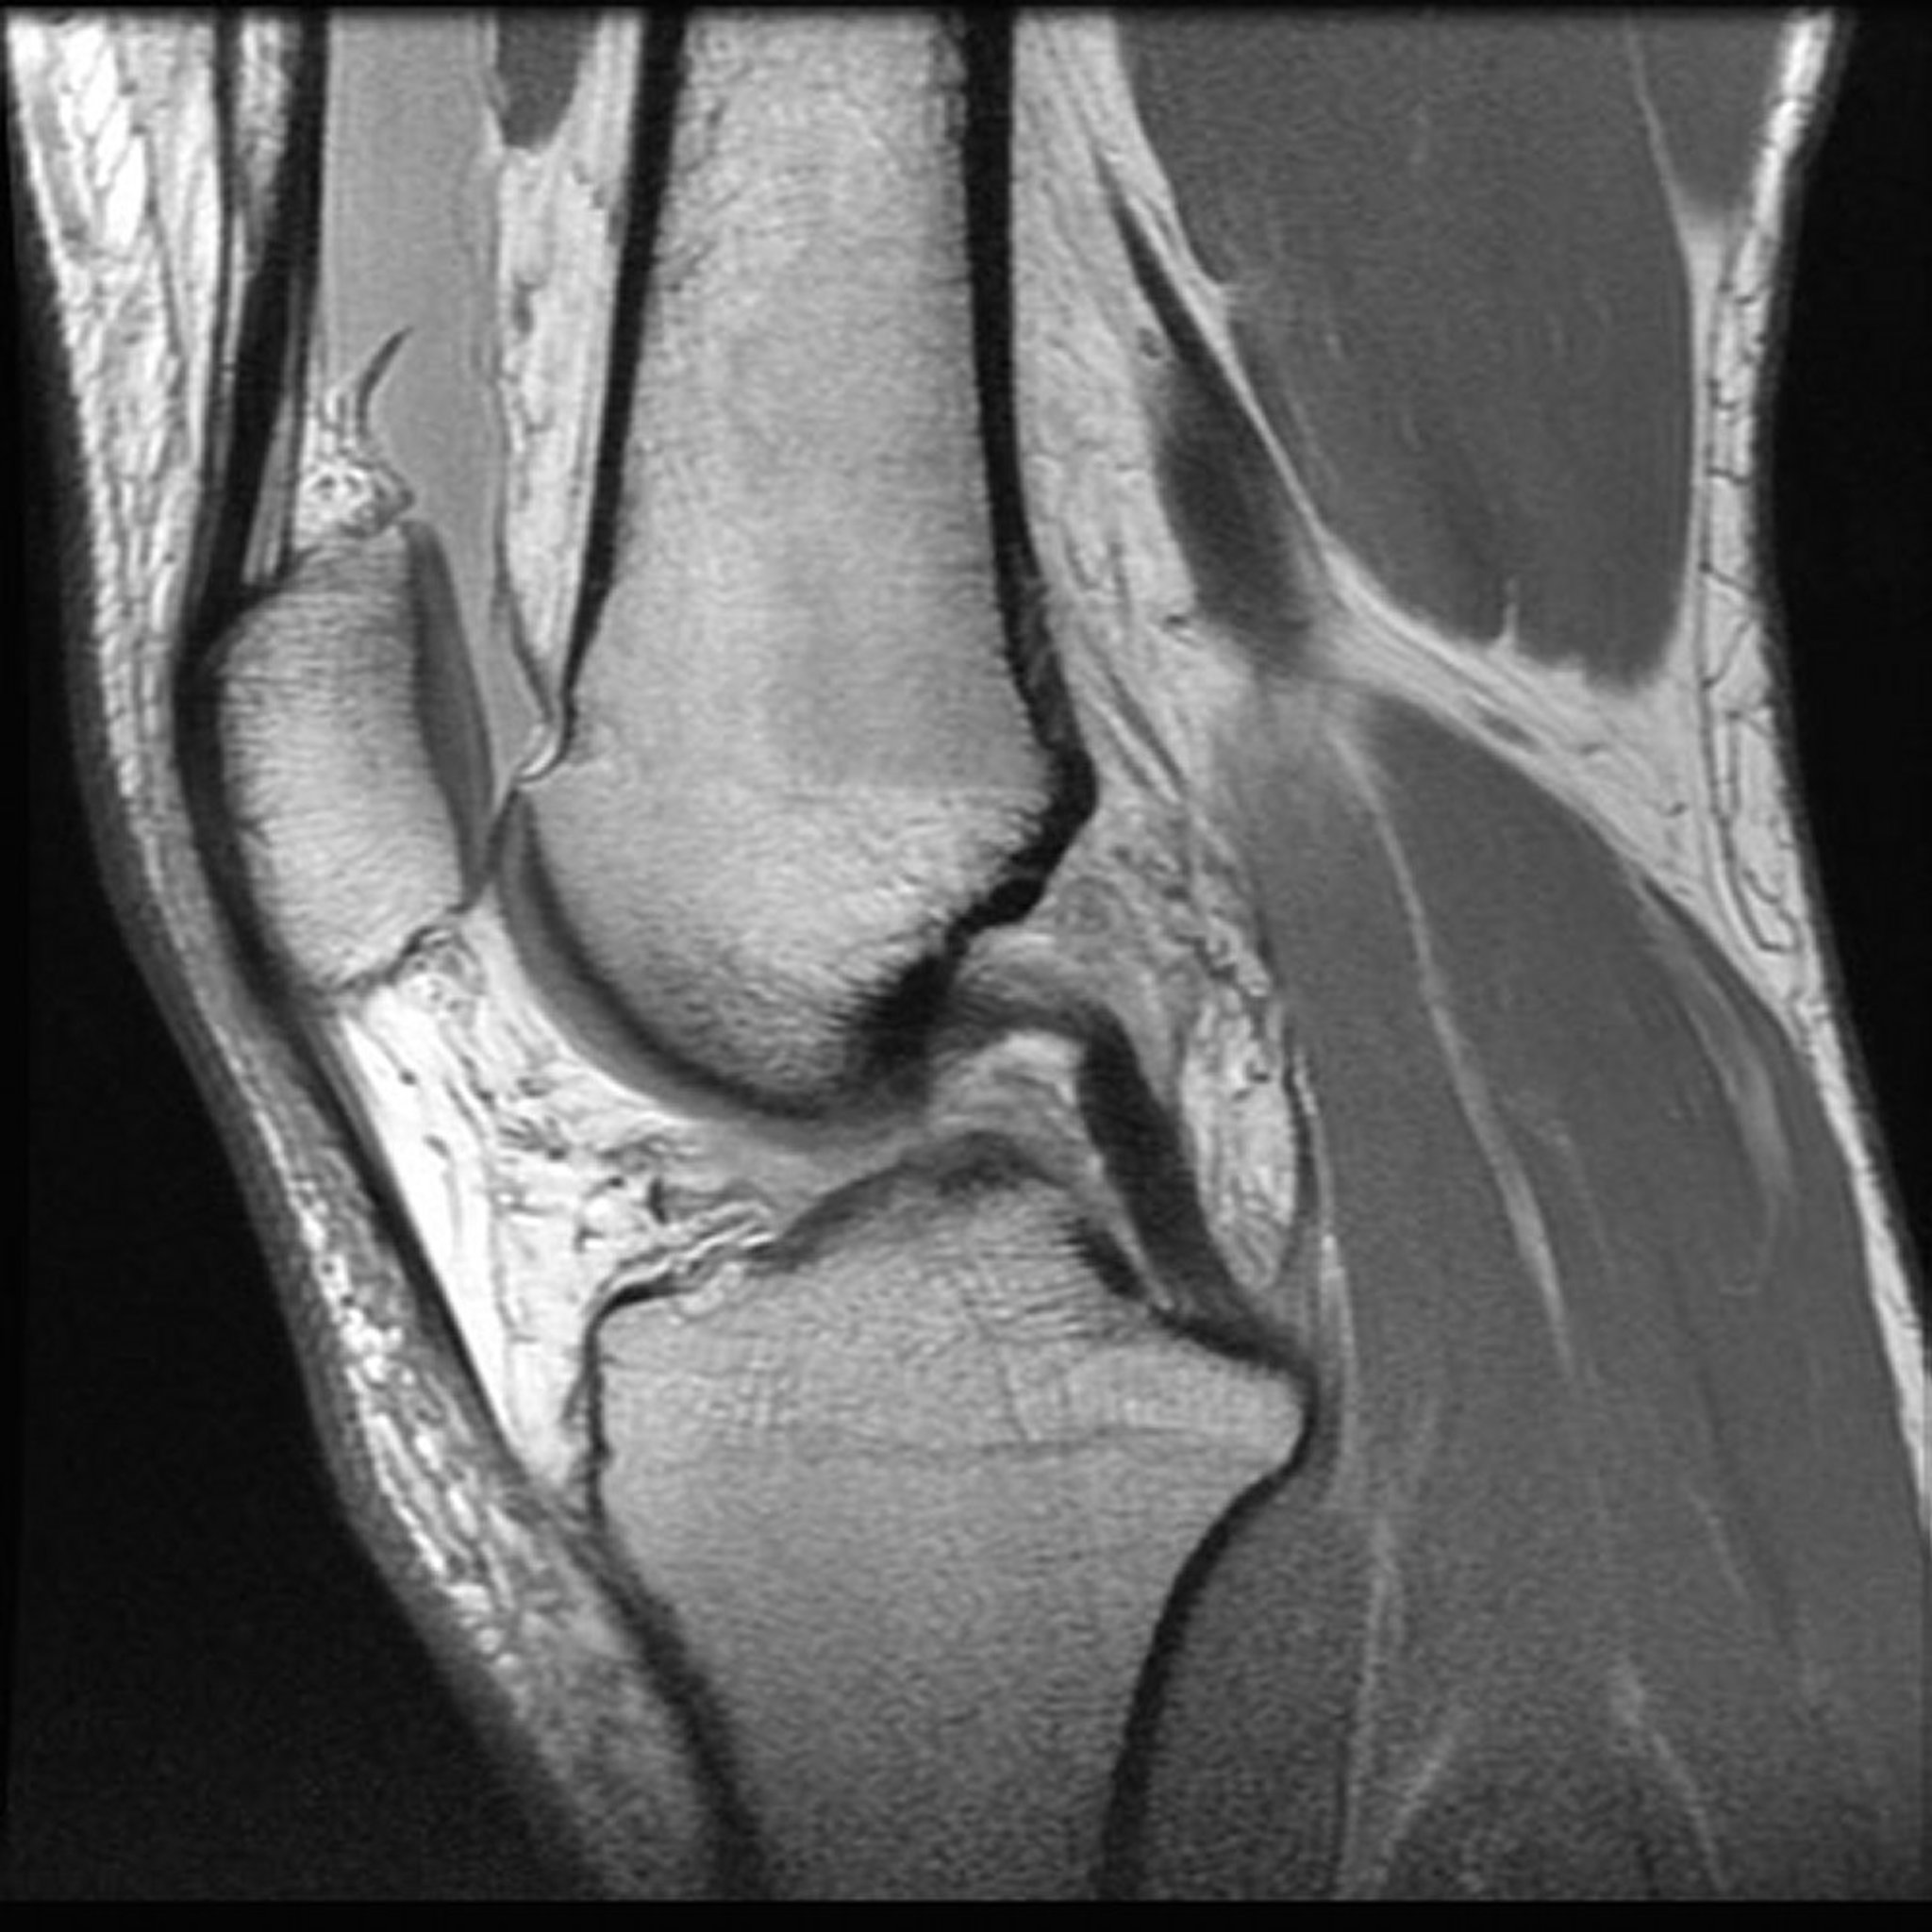

Gambar disediakan oleh Jon A. Jacobson, MD.

Membantu dokter mengevaluasi ketidaknormalan sendi (seperti robekan ligamen atau kartilago pada lutut) dan terkilir

MRI yang dilakukan setelah agen kontras gadolinium diinjeksikan ke dalam vena membantu dokter mengevaluasi peradangan, tumor, dan pembuluh darah. Menyuntikkan agen ini ke sendi akan membantu dokter mendapatkan gambaran yang lebih jelas tentang ketidaknormalan sendi, terutama jika bersifat kompleks (seperti pada cedera atau degenerasi ligamen dan tulang rawan pada lutut).